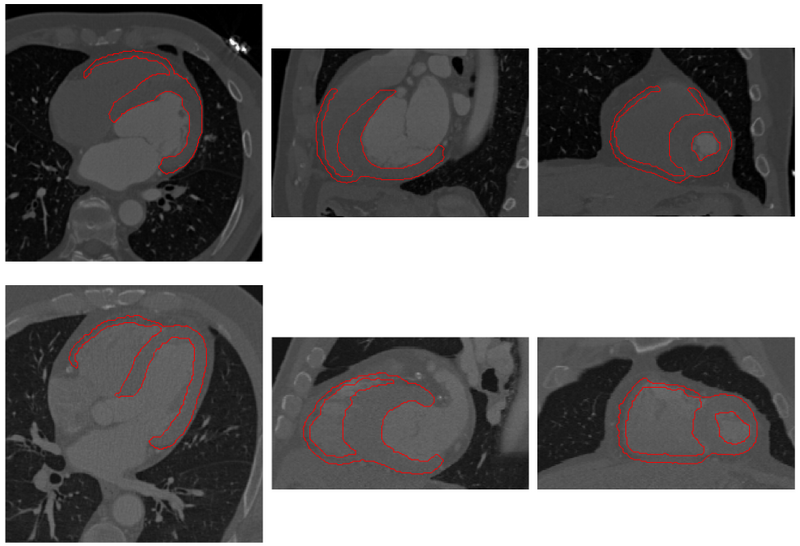

Extracting the myocardial wall of the left (LV) and right (RV) ventricles are important steps in the diagnosis of cardiac diseases. In this paper, we we propose an method for automatically extracting the ventricles from cardiac CT images, which integrates region growing with shape segmentation in a natural way. In this framework, the shape segmentation provides seed regions for region growing while the latter reconstructs a heart surface for shape decomposition.

In the method, the left and right ventricles are located sequentially, in which each ventricle is detected by first identifying the endocardial surface and then segmenting the epicardial surface. To this end, the endocardial surfaces are localized using their geometric features obtained on-line from a CT image. After that, a variational region-growing model is employed to extract the epicaridal surfaces of the ventricles. In particular, the location of the endocardial surface of the left ventricle is determined using an active contour model on the blood-pool surface constructed via thresholding. To localize the right ventricle, the active contour model is performed on a heart surface extracted based on the left ventricle segmentation result.

Results